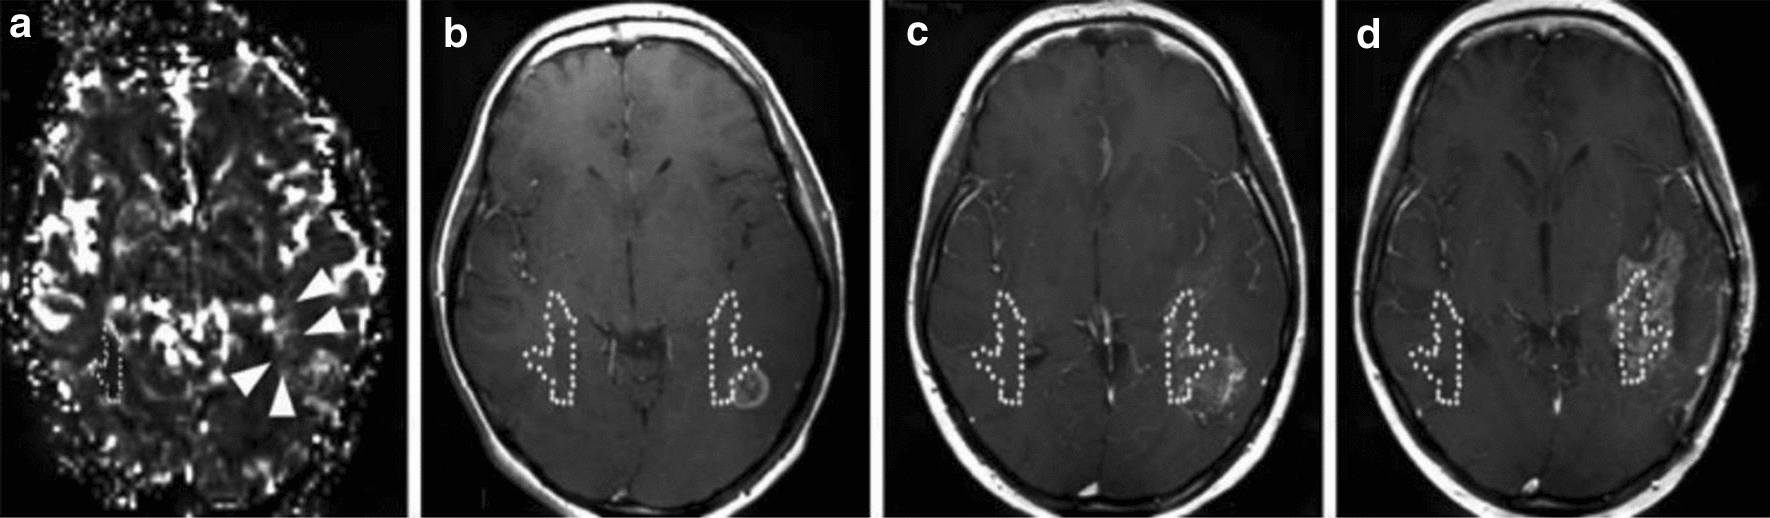

Multi-voxel MRS has the potential to identify and delineate substantial tumour infiltration and high-risk regions for recurrence. The feasibility of target delineation with multi-voxel proton MRS was first explored by Pirzkall et al. [92]. On average, the volume delineated on proton MRS was 58% of the volume based on T2-weighted imaging. Metabolic active disease (i.e., regions with abnormal Cho/NAA ratios), however, was still observed to extent ipsilaterally beyond the T2-weighted delineation in 9 out of 12 patients with glioblastoma. On contrast-enhanced T1-weighted MR imaging, the extension beyond the T1-weighted volume was not as great as was seen with grade III patients. Cordova et al. developed an imaging pipeline utilizing high resolution (0.1 cm3 nominal voxel size) spectroscopic imaging to generate whole-brain metabolic maps and evaluated the correlation between proton MRS biomarkers and Sox2 density, a normalized metric of tumour infiltration, in tissue samples of 13 patients with glioblastoma [93]. Various metabolic markers showed significant correlations, but Cho/NAA exhibited the strongest association with tumour infiltration (ρ = 0.82, p < 0.0001). During follow-up of these patients, 5 of the 13 patients had T1-weighted contrast-enhancing progression at the time of analysis. All patients showed T1-weighted contrast-enhancing progression in regions that exhibited Cho/NAA abnormalities before radiotherapy was given (see Fig. 7). A similar correlation between regions with increased Cho/NAA and recurrence site was also observed by Park et al. and Czernicki et al. [94, 95].

Fig. 7

Pre-radiotherapy Cho/NAA abnormalities were observed and delineated (red contour). Pre-RT imaging shows that increased Cho/NAA ratios on the Cho/NAA map (third column) extended beyond the GTV on T1-weighted contrast enhancement (first column) and T2-weighted/FLAIR (second column). First recurrence on contrast-enhanced T1-weighted imaging after radiotherapy (fourth column) showed contrast-enhancing tumour development within the pre-radiotherapy increased Cho/NAA volume in 3 patients (ac) (reprinted with permission from Cordova et al. [93])

Bild vergrößern